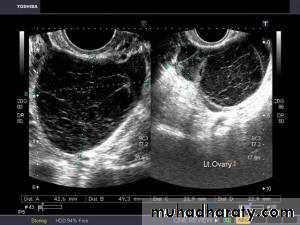

• Functional cysts of the ovary – Corpus Luteum cysts

Lt. adnexal cystic mass- Luteal cyst(Lt. ovary):

Rt. ovarian simple cyst: